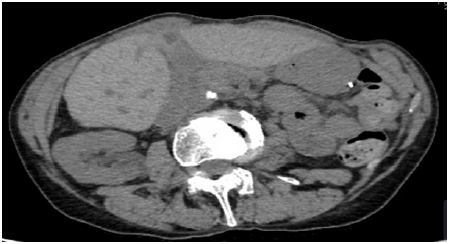

A 71-year-old woman with a history of Raynaud’s syndrome, pulmonary tuberculosis treated and declared cured, was followed up for a high-grade right ovarian cystadenocarcinoma with peritoneal carcinosis diagnosed in July 2013. The patient had received six cycles of neo-adjuvant chemotherapy carboplatin -paclitaxel followed by oncology surgery and then three adjuvant cycles. She underwent a monobloc excision of the right annex + hysterectomy + left annexectomy + ommentectomy. The pathology of the operating room was in favor of a right ovarian cystadenocarcinoma followed by 3 cycles of carboplatin paclitaxel as adjuvant, in In July 2014, the CA 125 was three times normal, associated with a hyper metabolic mediastinal lymph node flow on the PET scanner. The administration of carboplatin gemcitabine bevacizumab made it possible to have a radiological remission and a normalization of CA 125. The patient refused to continue chemotherapy since January 2016. In October 2017 a massive lymph node and peritoneal resumption with clear rise in CA125 (six times normal) was controlled by cycles of carboplatin paclitaxel. In October 2019, the patient presented melena associated with asthenia, weight loss and anemia with a hemoglobin at 8g/dl. The gastroscopy revealed a tumor formation under ulcerated mucosa, hemorrhagic, measuring 4cm of long axis, heterogeneous, with bumpy contours at the expense mainly of the second layer at the level of the gastric antrum (Figure 1). The biopsy with anatomopathological study revealed an infiltration of the gastric wall by poorly differentiated carcinomatous proliferation whose immunohistochemistry phenotype in favor of an ovarian origin whose positivity of WT1 and p53 point towards a high rank serious carcinoma (Figure 2) . The TAP scanner showed a gastric mass with lymph node metastasis and peritoneal carcinosis (Figure 3). The recurrence of melena with deglobulisation at 5.4g/ dl, required the achievement of an endoscopic hemostasis by plasma of Orgon and a transfusion of the pellet whose progress was favorable. Weekly gemcitabine chemotherapy was adopted, but the disease progressed rapidly. The patient died 4 months later.

Figure 1: Gastroscopy with endoscopy have highlighted the presence of a tumor formation under ulcerated mucosa measuring 4cm of long axis, heterogeneous with bumpy contours mainly depending on the 2nd layer at the level of the gastric antrum.